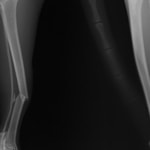

症例3:キルシュナーワイヤーのピンニングによる整復

ペルシャ猫 11ヶ月齢 雄

他院にて左大腿骨遠位の成長板骨折(salter-harrisⅠ型)が認められており、治療相談を目的として来院。当院にて、キルシュナーワイヤーを用いたピンニングにより骨折部位の整復を行いました。術後の経過は良好で、現在も経過観察中です。

術前レントゲン

術後レントゲン